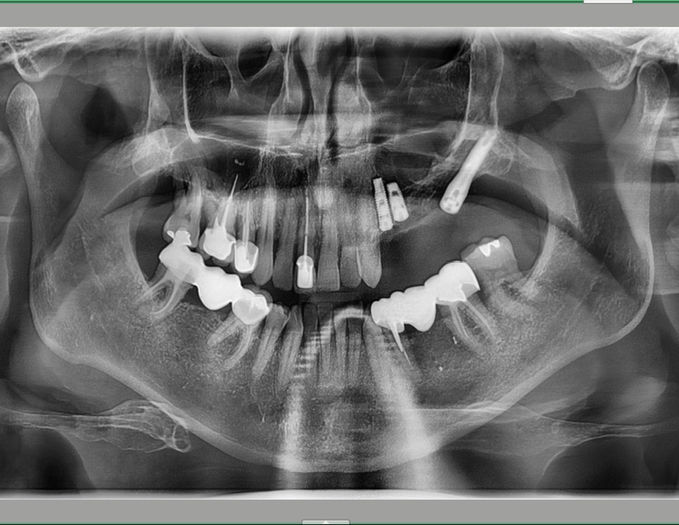

Ce cas illustre une réhabilitation quasi totale du maxillaire et de la mandibule à l'aide d'implants dentaires.

Les dents naturelles, compromis par une maladie parodontale avancée, ont été extraites.

Une planification implantaire guidée a permis une mise en place précise des implants, optimisant leur position et leur stabilité.

Des bridges implanto-portés ont été utilisés pour restaurer l'esthétique et la fonction occlusale.

Cette solution offre un confort masticatoire proche des dents naturelles et améliore significativement la phonation.

Elle permet également de préserver l'os alvéolaire, limitant la résorption osseuse à long terme.

Le résultat final est fonctionnel, stable et esthétique, apportant au patient une qualité de vie remarquable.